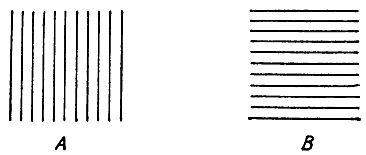

При сильном астигматизме человек видит четко, например, только вертикальные линии, а горизонтальные видит нерезко, или наоборот (рис. 6).

Рис. 6. Астигматический глаз видит фигуру А так, как она изображена справа.

Астигматизм резко выраженный исправляется очками с цилиндрическими стеклами, которые преломляют световые лучи только в направлении, перпендикулярном к оси цилиндра.